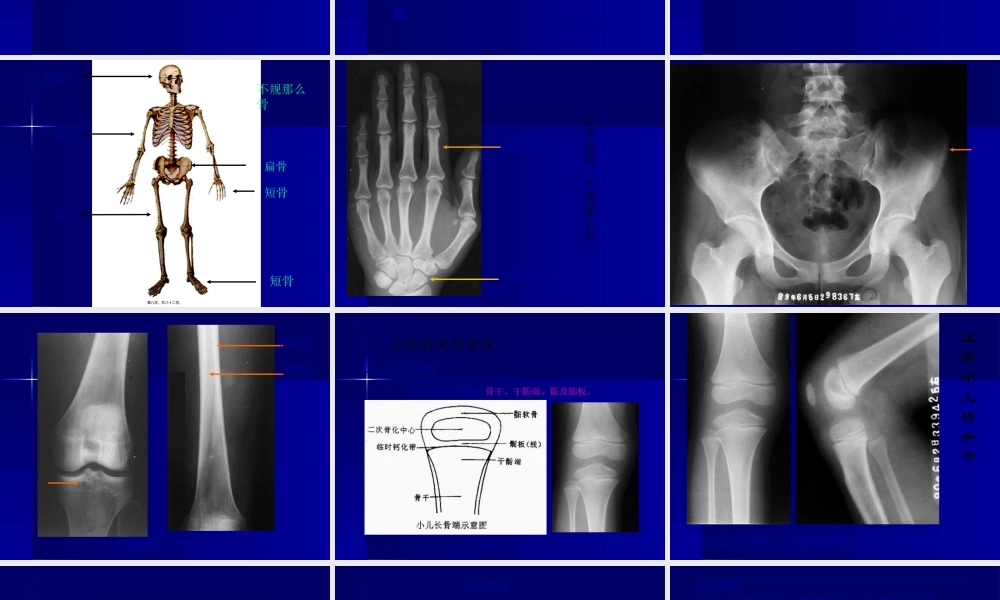

第九章骨骼肌肉系统实习欢送参与!昆明医科大学第一附属医院医学影像科第一页,共八十二页。实习一检查方法与正常表现【目的要求】1、了解骨及关节的不同成像技术的临床应用,熟悉X线检查方法〔重要和首选的检查方法〕。CT为平片的重要补充,对于解剖结构比较复杂的部位或显示软组织病变可首先选用。对骨髓病变、评价关节软骨疾患有优势。?医学影像诊断学?-骨骼肌肉系统第二页,共八十二页。2、掌握:四肢长管状骨的正常X线表现及各部位名称、儿童骨关节的X线解剖特点〔骨干、干骺端、骨骺板、骨骺〕、脊柱正常X线解剖各部位名称;3、熟悉四肢各关节的正常X线表现及名称;4、了解儿童骨龄的计算。第三页,共八十二页。【见习内容】1、儿童、成人的四肢长管状骨的正常X线表现〔DR片〕;分析骨的结构如骨皮质、骨松质、骨小梁、骨髓腔。识别各骨的形态,如胫骨、腓骨、尺骨、桡骨、股骨等。2、正常儿童四肢骨:儿童长管状骨的X线解剖特点〔骨干、干骺端、骨骺板、骨骺〕;〔DR片〕;识别儿童四肢骨在形态和结构上的主要特征。注意不同年龄儿童的骨骺及骺线的发育特征。了解骨龄测量对骨病的诊断意义。第四页,共八十二页。3、正常四肢关节:观察骨端、关节间隙、周围软组织。儿童、青少年及成人膝关节正侧位DR片。4、正常脊柱正侧位片:识别颈、胸、腰各椎体的形态特征。脊椎照片的分析步骤和脊椎各部位如椎体、椎弓、棘突、关节突以及椎间隙等的主要X线表现。腰椎正侧位及斜位DR片。第五页,共八十二页。医学影像诊断原那么1、熟悉正常影像表现2、识别异常影像表现3、异常表现的分析归纳4、疾病的综合诊断:注意“异病同影〞“同病异影〞第六页,共八十二页。医学影像诊断步骤1、了解影像学检查的目的2、明确图像的成像技术和检查方法3、全面观察和认真分析4、结合临床资料进行诊断第七页,共八十二页。长骨短骨不规那么骨扁骨扁骨长骨短骨第八页,共八十二页。正常短骨、不规那么骨短管状骨不规那么骨第九页,共八十二页。正常骨盆扁骨第十页,共八十二页。正常长骨骨小梁密质骨骨髓腔第十一页,共八十二页。一、长骨的X线表现1、小儿骨骼小儿长骨可分为:骨干、干骺端、骺及骺板。第十二页,共八十二页。正常小儿膝关节显示小儿长骨骨骺、二次骨化中心、骺板、干骺端和骨干第十三页,共八十二页。儿童骨骼的生长6M1Y2Y3Y4Y第十四页,共八十二页。小儿长骨第十五页,共八十二页。成人骨骼:骺与干骺端结合,骺线消失,分骨干和骨端;第十六页,共...

2、本站所有内容均由合作方或网友上传,本站不对文档的完整性、权威性及其观点立场正确性做任何保证或承诺!文档内容仅供研究参考,付费前请自行鉴别。

3、如文档内容存在违规,或者侵犯商业秘密、侵犯著作权等,请点击“违规举报”。

碎片内容

蜗牛文库的最新文档

二年级数学下册其中检测卷二年级数学下册其中检测卷附答案#期中测试卷.pdf

10.00金币

0下载